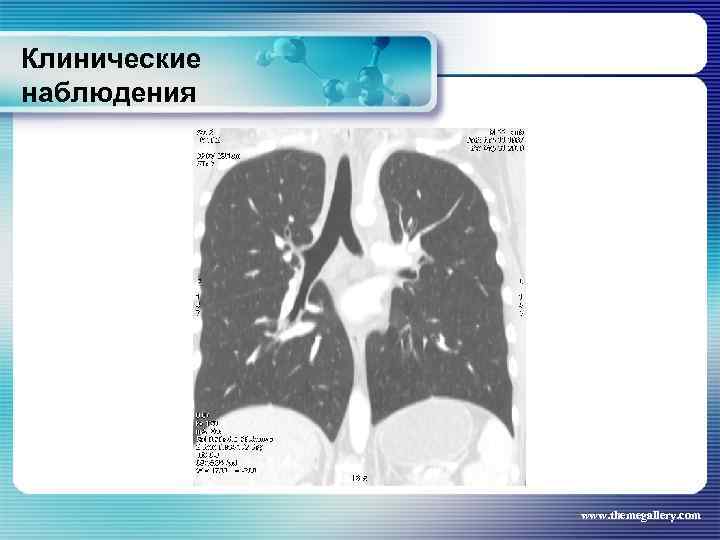

Клинические наблюдения Больной М. , 22 лет Заболел в январе 2010 года, когда появился мучительный кожный зуд, похудание, прогрессивный рост лимфатических узлов на шее, затрудненное дыхание. Самостоятельно обратился в поликлинику, направлен в гематологическое отделение. Выполнена биопсия шейного лимфатического узла: Лимфома Ходжкина. , нодулярный склероз Grade I. Уже отделении появилась лихорадка. При лабораторном обследовании выявлены признаки выраженной активности процесса. Результаты лучевого обследования: www. themegallery. com

Клинические наблюдения Больной М. , 22 лет Заболел в январе 2010 года, когда появился мучительный кожный зуд, похудание, прогрессивный рост лимфатических узлов на шее, затрудненное дыхание. Самостоятельно обратился в поликлинику, направлен в гематологическое отделение. Выполнена биопсия шейного лимфатического узла: Лимфома Ходжкина. , нодулярный склероз Grade I. Уже отделении появилась лихорадка. При лабораторном обследовании выявлены признаки выраженной активности процесса. Результаты лучевого обследования: www. themegallery. com

Клинические наблюдения Больной М. , 22 лет По результатам обследования сформулирован клинический диагноз: лимфома Ходжкина, нодулярный склероз, Grade I, III В стадия с поражением подчелюстных, шейных, надключичных лимфатических узлов с обеих сторон, подмышечных, переднегрудных, парастернальных, внутригрудных и абдоминальных лимфатических узлов, средостения. Было проведено 8 циклов BACOPP, на фоне лечения осложнение: полинейропатия рук, а затем асептический некроз головки правой бедренной кости. На фоне терапии отмечена положительная динамика как лабораторных данных, так и результатов лучевого обследования. Констатирована ремиссия www. themegallery. com

Клинические наблюдения Больной М. , 22 лет По результатам обследования сформулирован клинический диагноз: лимфома Ходжкина, нодулярный склероз, Grade I, III В стадия с поражением подчелюстных, шейных, надключичных лимфатических узлов с обеих сторон, подмышечных, переднегрудных, парастернальных, внутригрудных и абдоминальных лимфатических узлов, средостения. Было проведено 8 циклов BACOPP, на фоне лечения осложнение: полинейропатия рук, а затем асептический некроз головки правой бедренной кости. На фоне терапии отмечена положительная динамика как лабораторных данных, так и результатов лучевого обследования. Констатирована ремиссия www. themegallery. com

Клинические наблюдения Тот же пациент В сентябре-ноябре 2010 года выполнена телегамматерапия на шейные, надключичные лимфатические узлы, средостение (СОД – 36 Гр) и на аксилярную область (СОД – 24 Гр). Абдоминальные лимфатические узлы не облучали, т. к. они регрессировали на фоне ПХТ. Результаты лучевого обследования в настоящее время: www. themegallery. com

Клинические наблюдения Тот же пациент В сентябре-ноябре 2010 года выполнена телегамматерапия на шейные, надключичные лимфатические узлы, средостение (СОД – 36 Гр) и на аксилярную область (СОД – 24 Гр). Абдоминальные лимфатические узлы не облучали, т. к. они регрессировали на фоне ПХТ. Результаты лучевого обследования в настоящее время: www. themegallery. com